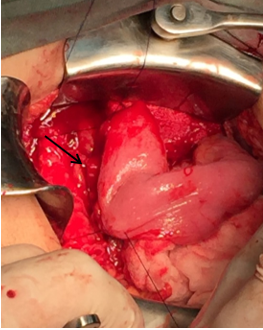

Incisión mediana supraumbilical, apertura del ligamento gastrocólico, movilización del duodeno mediante maniobra de Kocher. Identificación del páncreas, que se presentó de consistencia indurada, localización del conducto de Wirsung mediante palpación y ecografía intraoperatoria, se confirma su topografía mediante punción con aguja fina. Apertura pancreática longitudinal con electrocauterio a nivel del cuello y cuerpo hasta el conducto de Wirsung que se abre por su cara anterior (aprox. 3 cm). Identificación y aspiración de detritus celulares de su luz, sin litiasis a dicho nivel . Biopsia incisional de tejido pancreático.

Sección del intestino delgado a nivel de la segunda asa yeyunal, con cierre del extremo distal de la misma y ascenso del asa por vía transmesocólica. Apertura del asa por su borde antimesentérico y confección de la anastomosis yeyuno-pancreática (Wirsung) latero-lateral con puntos separados con poliglactina en 2 planos (Figura 3).